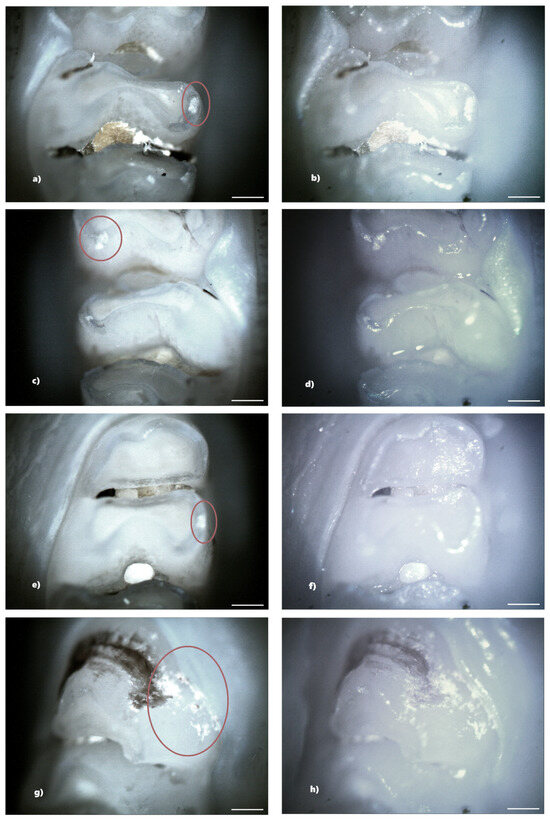

Figure 8. Demineralization on the occlusal surface of some molars (a,e,i—PLM image, cross polarizers, 4× objective; c,g,k—PLM image, cross polarizers, 10× objective; b,f,j—BFM image, 4× objective; d,h,l—BFM image, 10× objective). Scale bar represents 500 μm.

In the standard dose cefaclor group (20 mg/kg), 14 rats (93.33%) showed at least one clinical form of DDE. Of these, five rats showed demineralization and seven rats showed both clinical forms of DDE. Within this group, from a total number of 240 teeth, 45 teeth (18.75%) presented at least one type of DDE, respectively, 20 incisors (44.44%) and 25 molars (55.56%), and as a clinical form of DDE, 15 teeth (33.33%) showed hypoplasia (2 incisors and 13 molars) and 30 teeth (66.67%) showed demineralization (18 incisors and 12 molars). Among the 45 affected teeth, 10 teeth showed DDE on two surfaces, resulting in 55 affected tooth surfaces (Figure 8).